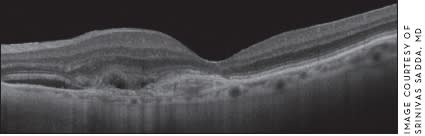

Figure 2. Spectral domain OCT image of an eye with a choroidal neo vascular lesion and a thin choroid.